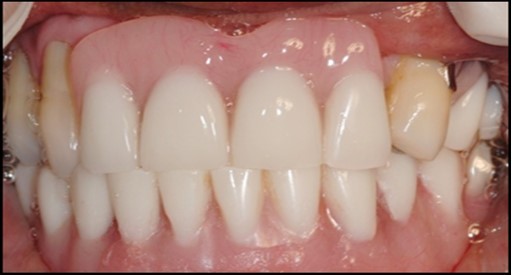

A transferable mark with an indelible pencil is placed on top of each ball abutment and old denture is seated to ideally determine the location for attachment housings. It is followed by preparation of recesses in the intaglio surface of the denture to accommodate the housings (Figure 7B). Lingual vent holes are made for escape of excess acrylic. Placement of nylon processing insert into each of the housings is done with insert seating tool. Figure 8 Seating of the attachment housing onto each ball type abutment is done (Figure 9). Undercuts are blocked out under the housing and soft tissue to prevent acrylic resin from locking the denture onto the abutment. Application of self curing acrylic is done into recessed area and around titanium housings for bonding of the housings to denture. Insertion of denture was done and guiding the patient into proper occlusion with the opposing arch. After the curing of acrylic, denture is removed. Excess acrylic is removed around the housings and lingual vent hole later it is polished (Figure 10). Replace nylon retention insert instead of processing insert into the housings. The insert must seat securely in place and be in level with the housings rim. Overdenture is seated over the ball abutments (Figure 11). Proper instructions have been given to the patient on insertion and removal of prosthesis (Figure 12). The patient was recalled at 1 week, 3 weeks, 3 months, 6 months follow up appointments.

1. Full arch implant supported fixed prosthesis, Implant supported overdentures.14, 15 (Figure 12)

General criteria for survival and success of implants have been used to evaluate the efficacy of immediately loading mandibular implants. For example, survival criteria include how the implant performs, particularly regarding the absence of pain, infection, and paresthesia. Implant immobility and the absence of periimplant radiolucency under radiography are 2 more criteria of implant survivability.6, 7 Success criteria include the additional element of absence of vertical bone loss; specifically, less than 1 mm during the first year and less than 0.2 mm annually thereafter. Granted that success rates for immediatel oading of implants in the edentulous mandible are not as high as rates for the traditional 2-stage approach, conditions nevertheless often warrant the 1-stage surgical option described here.7, 8, 9 (Figure 12).

Using 2 implants and retentive anchors for the retention of a mandibular complete denture is, in terms of immediate costs, one of the most affordable implant procedures. 8, 9, 14 With ideal placement of the implant, the stability of the prosthesis is excellent and the lingual dimensions of the denture can in some cases be reduced to the level of mylohyoid line, providing more space for the tongue and greater comfort than with conventional complete dentures.8, 9, 10, 15 However, if the labial musculature is tense or the amount of attached gingiva is limited, the implants should not be placed too deep or too labially, which might prevent gingival growth over the abutments. In those cases, ball anchor abutments with elevated shoulders can be used to improve implant anatomy.8, 9, 10 (Figure 12).